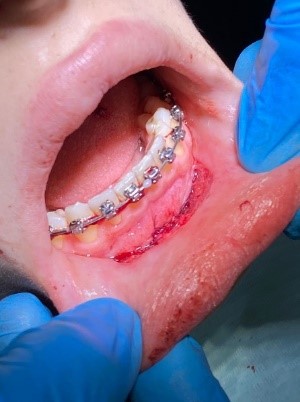

Клинический случай № 2. Пациентка 28 лет находится на ортодонтическом лечении. Пришла на прием по рекомендации врача-ортодонта. Осмотр преддверия полости рта показал недостаточное количество прикрепленной десны во фронтальном отделе нижней челюсти. Констатировано мелкое преддверие полости рта, 3 мм прикрепленной десны (рисунок 3a). Рекомендовано углубление преддверия путем вестибулопластики. Сопутствующие соматические заболевания отрицает. Результаты общего анализа крови без видимых патологий.

Проведена операция по углублению преддверия полости рта по Эдлану – Мейхеру. Рассечение и смещение мышечных тяжей апикально (рисунок 3b). Наложение швов с фиксацией слизистого лоскута к надкостнице (рисунок 3c). После снятия швов даны рекомендации (рисунок 3d).

a

b

c

d

Рис. 3. Мелкое преддверие полости рта: a – мелкое преддверие; b – смещение мышечных тяжей апикально; c – фиксация слизистого слоя к надкостнице; d – углубленное преддверие полости рта

Fig. 3. Small Oral Vestibule: a – small vestibule; b – pical displacement of muscle strands; c – fixation of the mucous layer to the periosteum; d – the deepened vestibule of the oral cavity